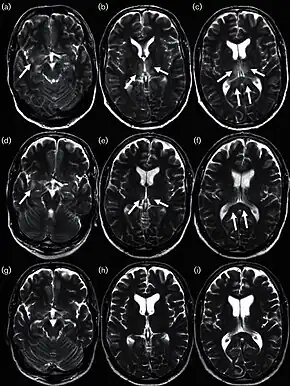

Influenza encephalitis MRI

In some cases, an autoimmune response to an influenza infection may contribute to the development of Guillain–Barré syndrome.[172] However, as many other infections can increase the risk of this disease, influenza may only be an important cause during epidemics.[172][173] This syndrome has been believed to also be a rare side effect of influenza vaccines. One review gives an incidence of about one case per million vaccinations.[174] Getting infected by influenza itself increases both the risk of death (up to 1 in 10,000) and increases the risk of developing GBS to a much higher level than the highest level of suspected vaccine involvement (approx. 10 times higher by recent estimates).[172][175]